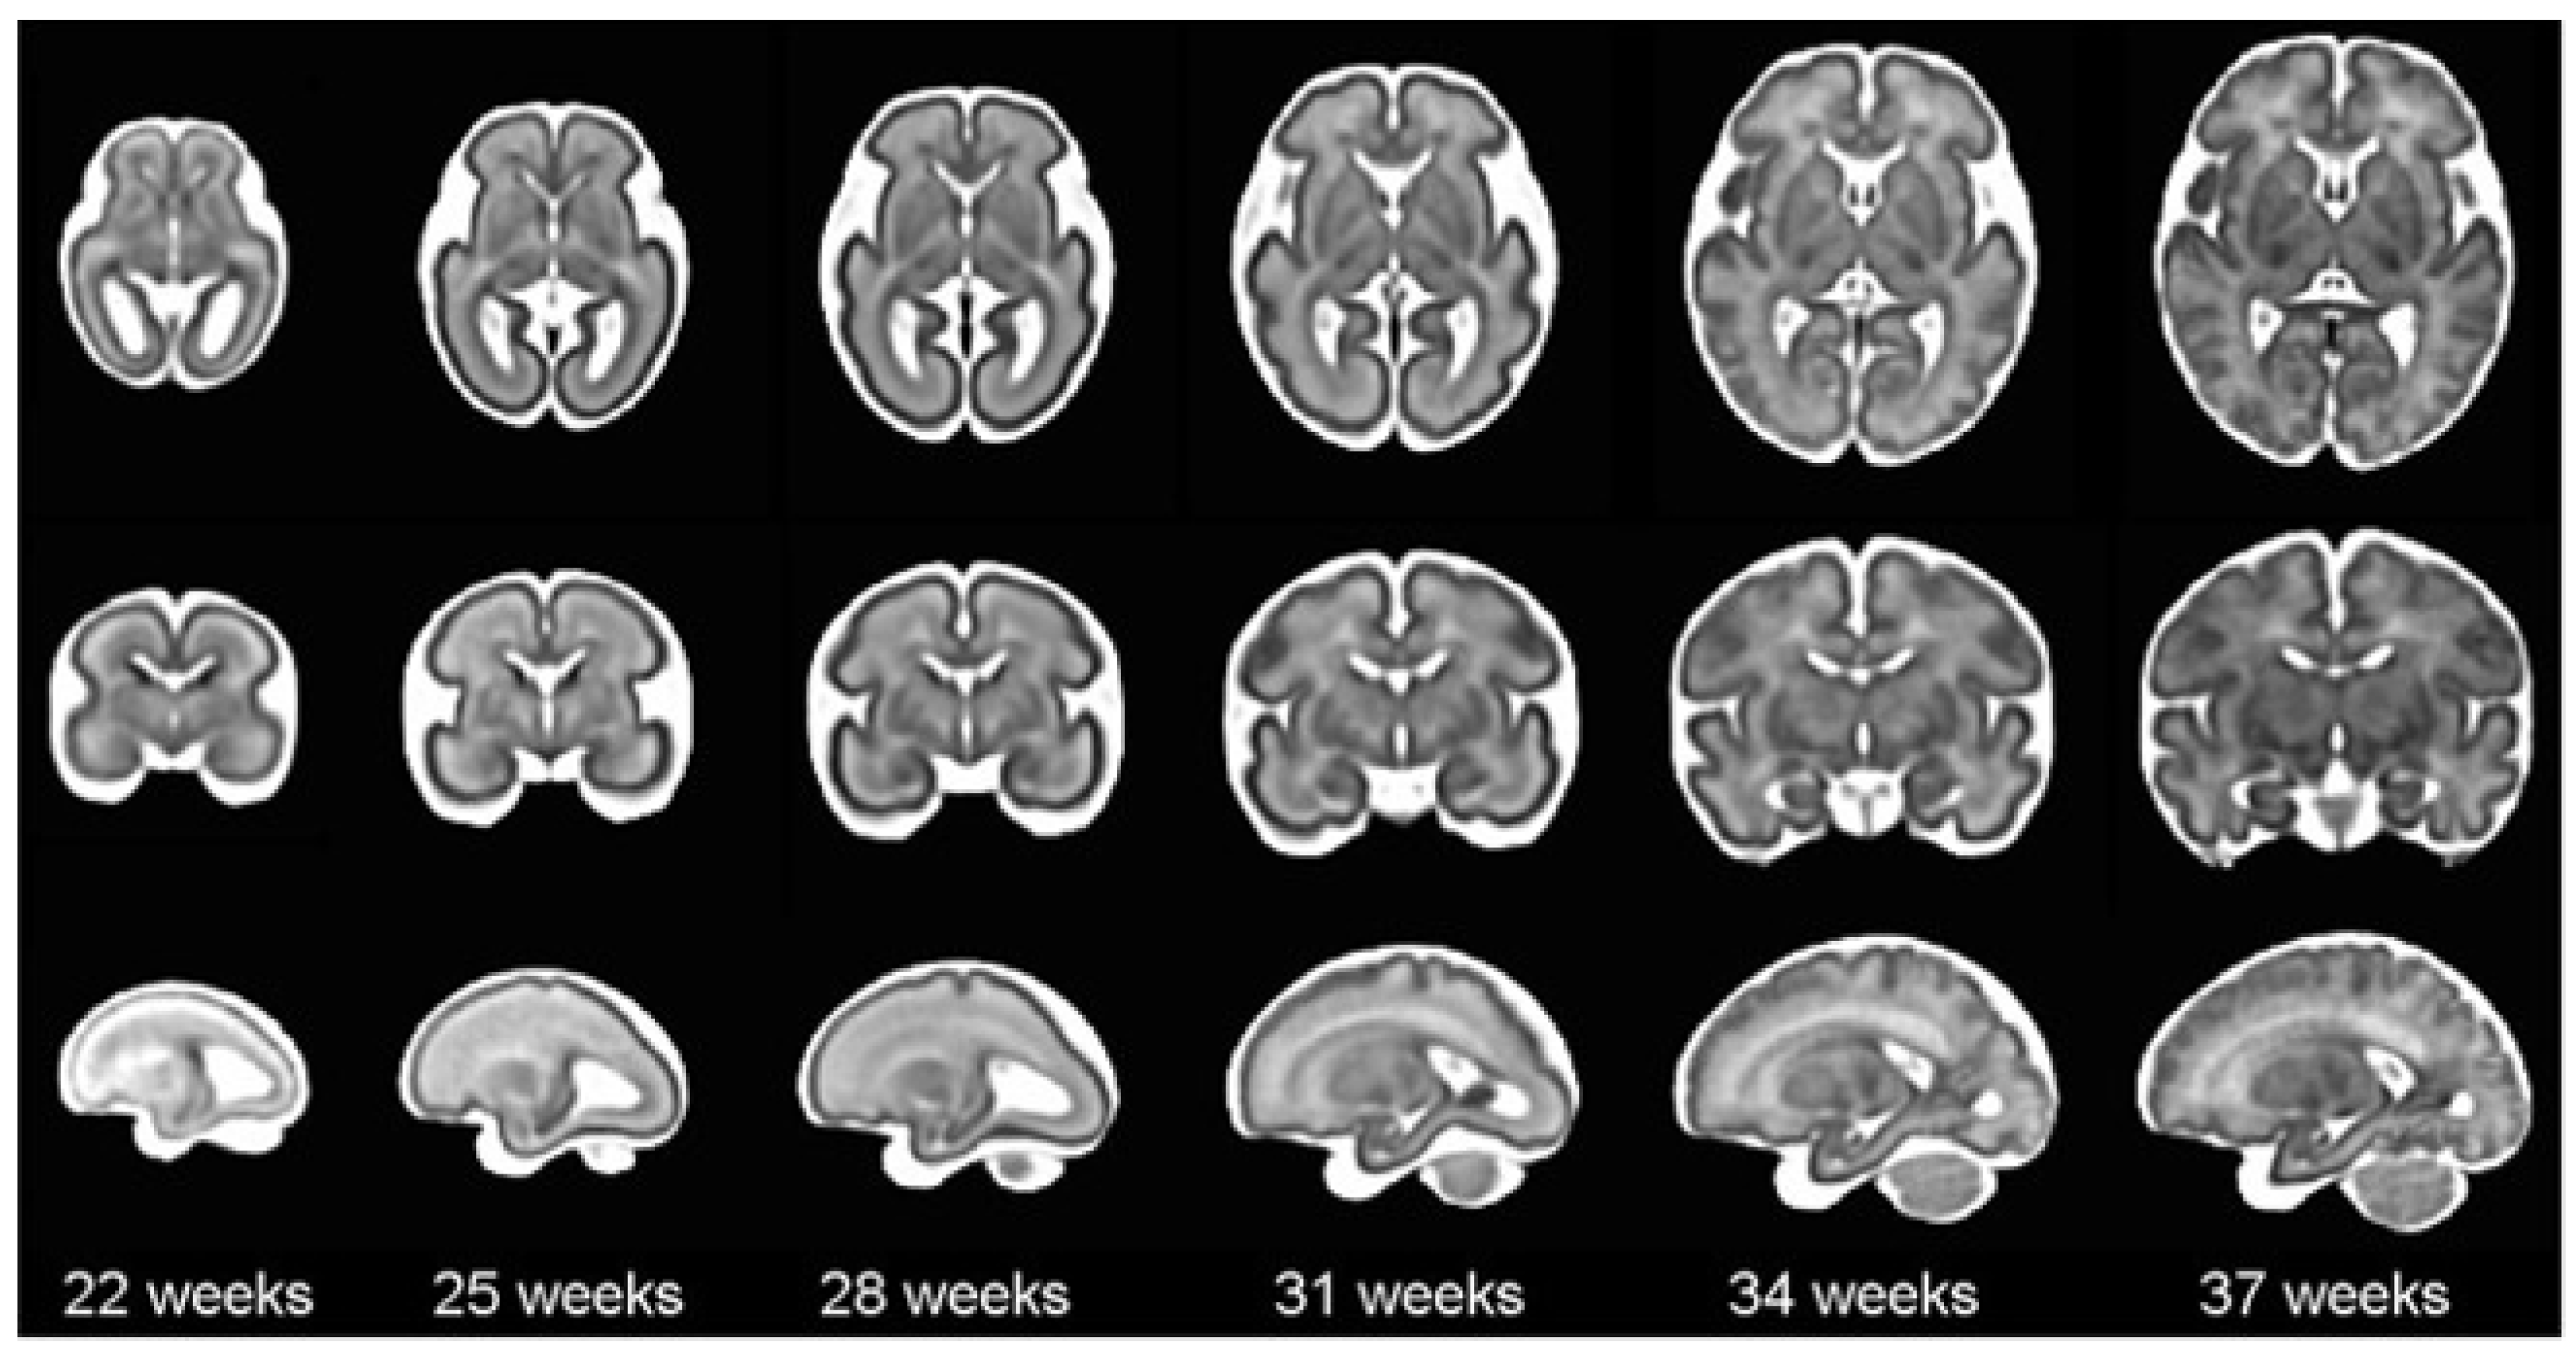

According to the World Health Organization (WHO), an estimated 13.4 million babies were born too early in 2020; that is more than one in ten babies [4]. Approximately 900,000 children died in 2019 of complications during preterm birth [5]. In this sense, it is worth mentioning that brain maturation is different when comparing a newborn that has completed nine months of gestation with a preterm baby that has grown outside the womb. Preterms are defined as babies born alive before 37 weeks of pregnancy are completed. There are sub-categories of preterm birth based on gestational age: Extremely preterm (less than 28 weeks), Very preterm (28 to 32 weeks), and Moderate to late preterm (32 to 36 weeks). An example of normal brain maturation in fetuses has been described using magnetic resonance imaging (MRI) techniques (Figure 1). To analyze the sulci of the brain during the maturation of the brain, the database is formed by two different planes, coronal or frontal and sagittal [6]. This concept refers to complex changes at specific stages of development whereby the cerebral cortex folds, forming sulci and gyri in order to increase the cerebral surface with a minor increase in volume. The process takes place during the last trimester of gestation, and it follows a specific sequence that allows us to date a specific brain base to its gyration status [7].

Figure 1. The spatio-temporal fetal brain magnetic resonance atlas (CRL fetal brain atlas) at six representative gestational ages: 22, 25, 28, 31, 34, and 37 weeks. Axial, coronal, and sagittal views of the atlas have been shown for each age point [7].